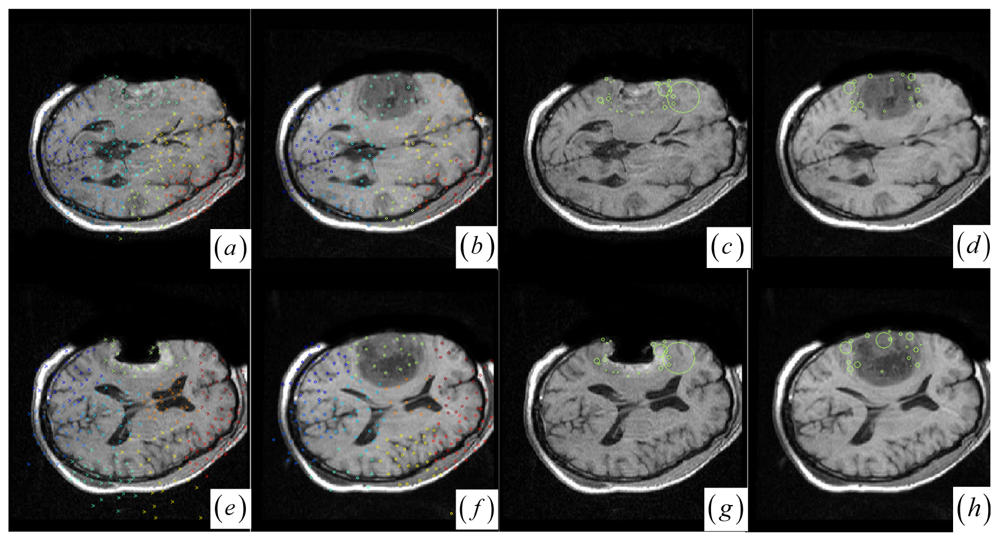

In contrast to four state-of-the-art intensity-based registration methods, including B-Spline with correlation ratio [56] (BCR), B-Spline with normalized MI (BMI) [34, 57], Demons (DEM) [58] and diffeomorphic Demons (DIF) [59], which are failed or unsatisfactory in tumor resection with outliers and local large deformation, our proposed method based on JSM & keypoint clustering (JKC) successfully model the tumor resection-induced brain shift (see Figures 34 and Table 1 cases 1–3). Table 1 summarizes the registration quality in terms of correlation ratio (CR) and normalized MI (NMI) [4, 60]. Figure 3a–d and Figure 4a–d show that the regions around the tumor areas have smoothly deformed to shift towards the tumor resection areas in the JKC registration results. The smoothly constructed deformation field is displayed by means of displacement vector field with variations of the vector color (from blue to red according to the displacement amplitude in pixels). The quality of these registration results also can be validated by the respective small CRs listed in the Table 1 cases 1–3. We also define the average error distance between the manually defined reference landmarks and the floating landmarks in the registered images (Figure 5 shows that most landmarks are around the tumor resection areas and the neighboring normal tissues), our method's average accuracy for the three cases of local large deformation (cases 1–3) achieves an average error distance of less than 1.2 pixel while the average accuracy for the two cases of small deformation achieves an average error distance of less than 1 pixel.

The BCR and BMI registration are implemented at two pass with the different transformation options (B-Spline degree for all axes: 1, 2; B-Spline control points for all axes: 8, 16; gradient descent minimize step size: 1.0, 0.5; gradient descent minimize maximum search steps: 10, 10) and the different iteration options (the convergence limit of minimum change rate for one iteration: 0.1, 0.01; maximum number of iterations: 10, 10) [57]. The dark areas on the deformation image (Figure 3f,h and Figure 4f,h) are related to the areas on the two images which did not perform a deformation during the registration or the deformation was relatively small. The light areas are related to the areas on the two images which perform a bigger deformation. In contrast to the BMI (Figure 3e,f and Figure 4e,f) that fails to compensate the local large deformation around the tumor areas, the BCR (Figure 3g and Figure 4g) can guide the anatomical structure deformation around the tumor resection regions (This also can be validated from the cases 1–3 at Table 1, at which the BCR have smaller CRs than the BMI, DEM and DIF). Nevertheless, the BCR has blurred and excessively shrunk the pre-operative anatomical structures around the tumor areas. From this experiment, we also confirm that the CR is more appropriate to be a similarity measure for the nonrigid monomodal registration of small structures than the NMI.

The DEM and DIF registration are conducted with a maximum step length of 2 pixels, 1.0 standard deviations of the Gaussian smoothing, a maximum number of 200 iterations and 0.001 intensity difference threshold. Treating each image as a set of iso-intensity contours and assuming the same anatomical point having the same intensity level in both images, the DEM and DIF easily distort the data to some extent, which may introduce strange artifacts similar to pieces of small mosaic patterns in the deformed pre-operative images (Figure 3i,k and Figure 4i,k). Additionally, the ”demons algorithm” with its large number of degrees-of-freedom allows to run into problems with the physical fidelity of the deformation field (Figure 4k and the DIF at case 2 in Table 1).

Figure 3. (a)–(b) Intra- and pre-operative MR images. (c) JKC. (d) Displacement vector field with the vector orientation and the variations of the vector color (the color scale encodes the norm of the displacement vector, in pixels). (e) BMI. (f) BMI deformation image. (g) BCR. (h) BCR deformation image. (i) DEM. (j) DEM deformation image (the color scale encodes the norm of the displacement vector, in pixels). (k) DIF. (l) DIF deformation image.